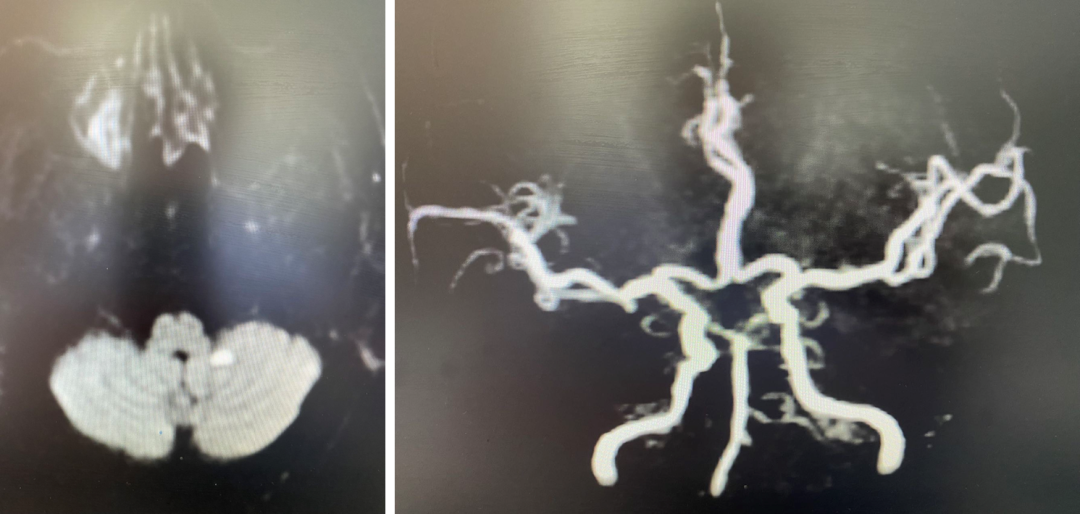

颅脑DWI+MRA:

导丝怎么扩【载药时代 球扩天下】NOVA DES®颅内药物洗脱支架在椎动脉颅内段重度狭窄的应用二例_https://www.jmylbn.com_新闻资讯_第20张

诊断

主要诊断:

1.右侧椎动脉V4段重度狭窄(90%);

2.高血压病2级 高危;

3.小脑梗死。